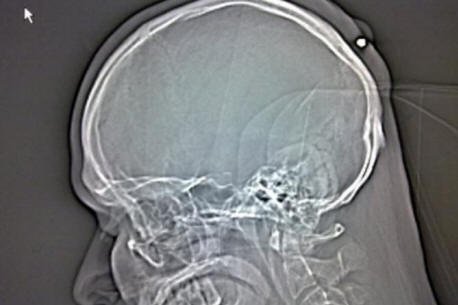

Autullo kieltäytyi uskomasta sitä sairaalaan viitaten lääkärit osoittivat hänelle: röntgenkuvauksessa oli selvää, että kahdeksan sentin senttinen rautakyntti kiinni aivan kallon sisään laatikot Dantea. Ennen kuin ambulanssi vei Autulloa toiseen klinikkaan Dante julkaisi siitä kuvan Facebook-sivulleen röntgenkuva.